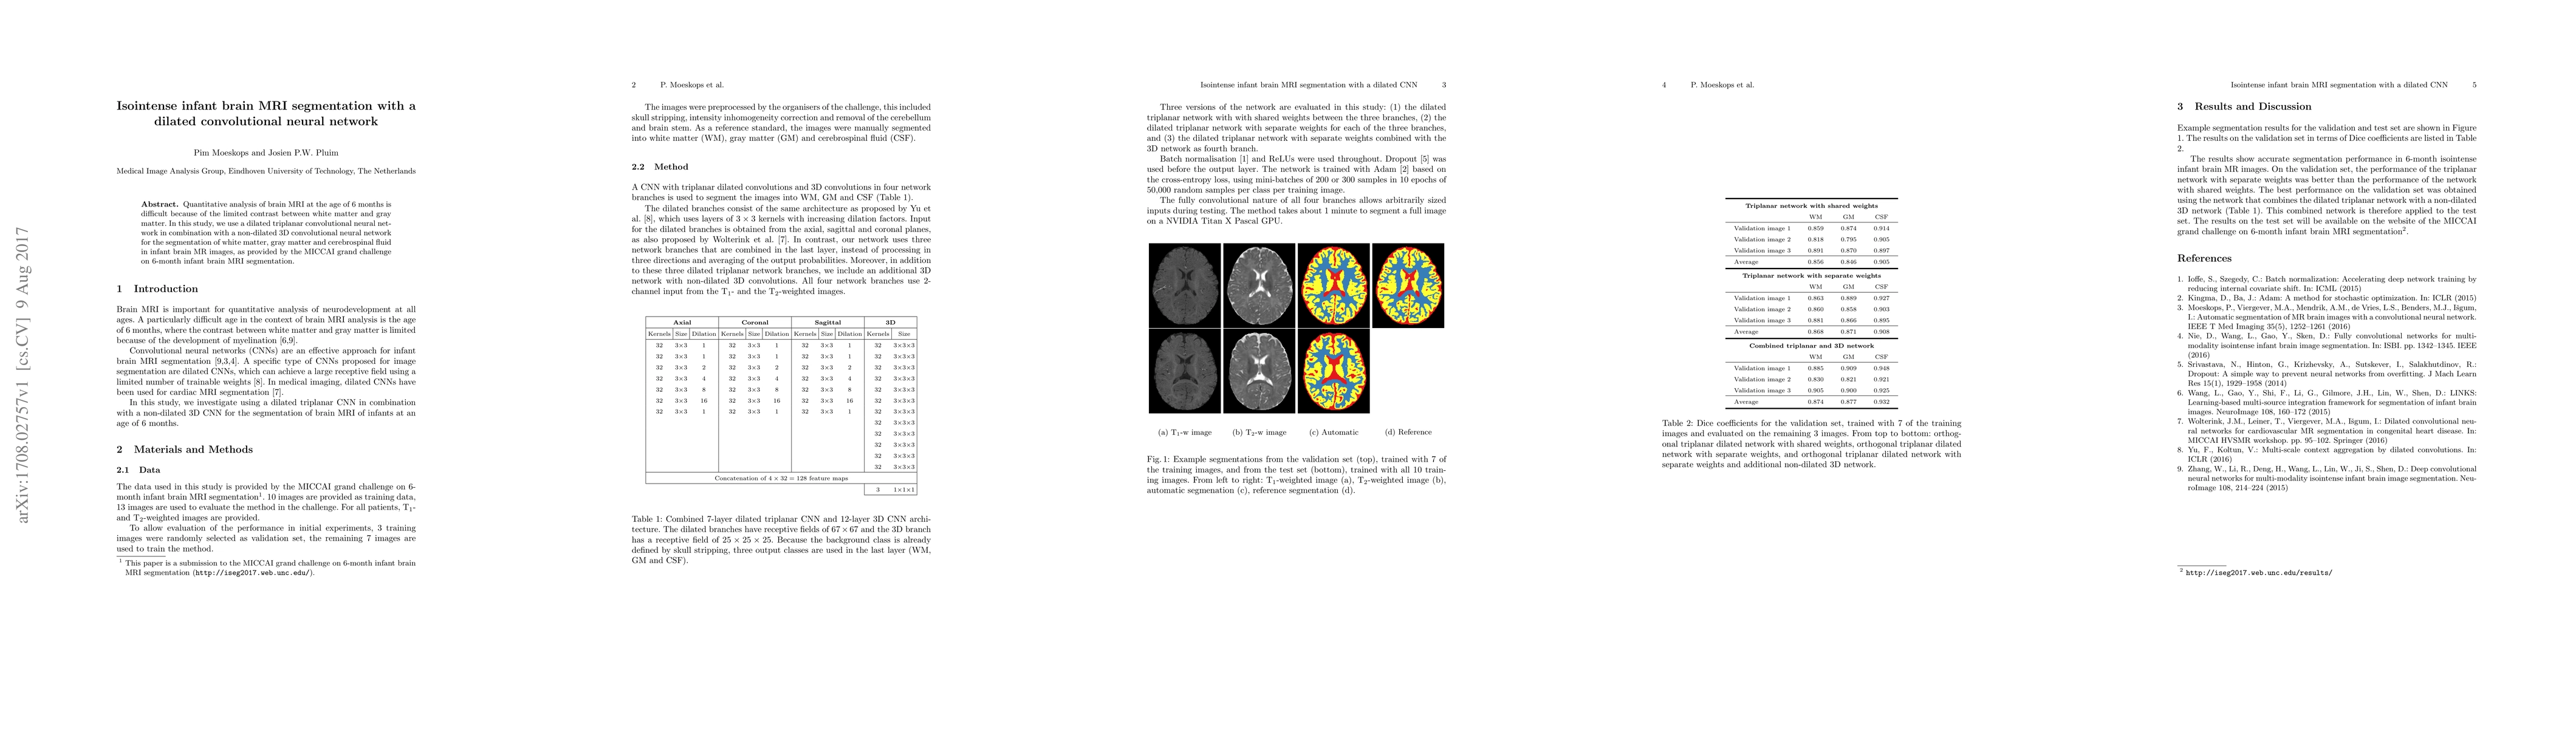

Quantitative analysis of brain MRI at the age of 6 months is difficult because of the limited contrast between white matter and gray matter. In this study, we use a dilated triplanar convolutional neural network in combination with a non-dilated 3D convolutional neural network for the segmentation of white matter, gray matter and cerebrospinal fluid in infant brain MR images, as provided by the MICCAI grand challenge on 6-month infant brain MRI segmentation.